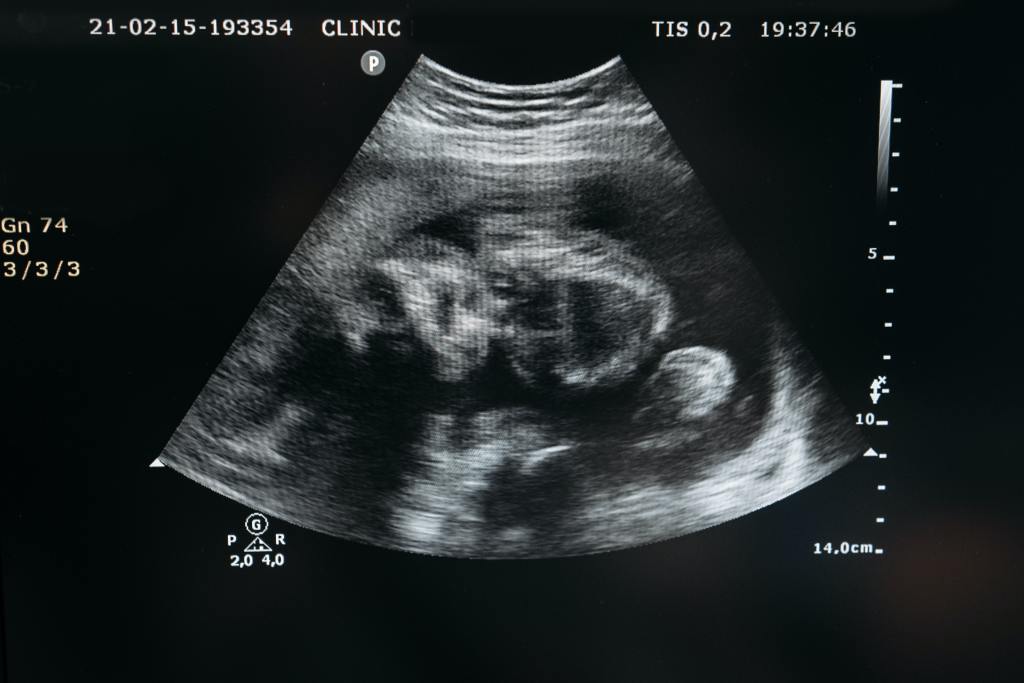

You may have heard it said that abortion stops a beating heart. That’s very true.

It’s possible to detect an embryo’s heartbeat from about the fifth week of pregnancy on. By the tenth week, the baby’s heart is fully formed.

The tiny heart is beating anywhere from 110 to 150 beats per minute to help supply blood to the fetus (the developing child is generally referred to as a fetus after the eight week).

Even at this early stage of life, critical functions are taking place to allow the child to live and continue developing.

Other milestones in the baby’s growth include the development of the neural tube in weeks five through eight. This includes the brain, the spinal cord, and other neural tissue of the central nervous system.

By the end of the second month, the fetus is about one inch long and weighs about 1/30th of an ounce.

During weeks nine through 12, the hands, fingers, feet, and toes are formed. Fingernails and toes are beginning to develop, and the reproductive organs are taking shape.

By the end of the third month, or the first trimester, the fetus is fully formed. All the limbs are in place and will continue to develop over the next few months.

Mother and baby are about one-third of the way through their pregnancy.

Rather, by emphasizing the early weeks of the child’s life in utero, you can see that there is much development and growth already taking place. The miracle of life is in full bloom inside the mother’s womb long before she begins to show her pregnancy.